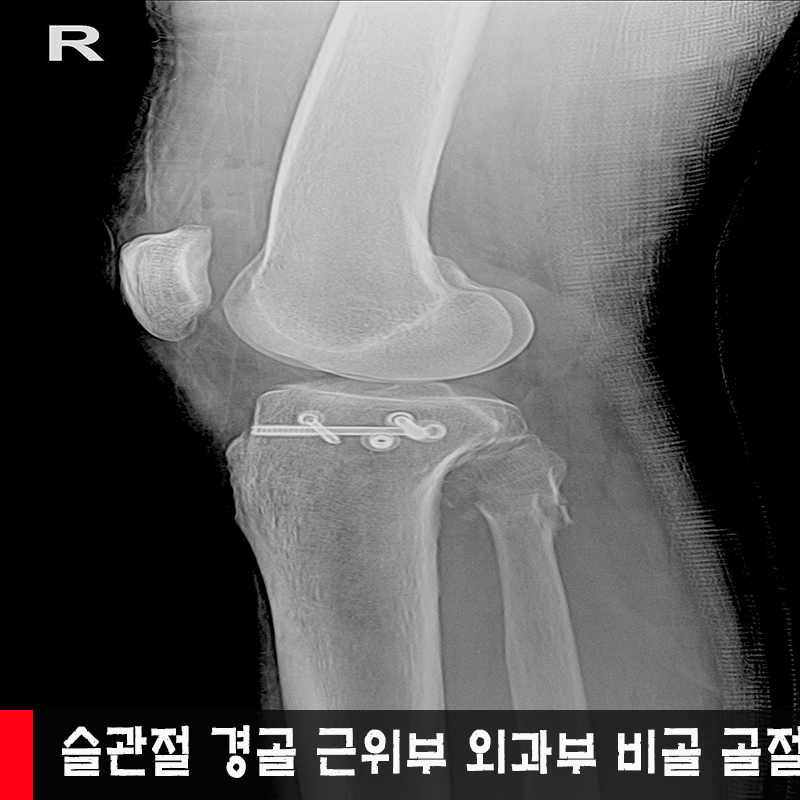

°ß°©°ñ °ñÀý, ¿ìÃø½½°üÀý °ß°ñ ±ÙÀ§

¿ÍºÎºÎ ¹× ºñ°ñ±ÙÀ§ °ñÀý, ½½°üÀý °ñÀý

¨è ¿ìÃø °ß°©°ñ üºÎ °ñÀý